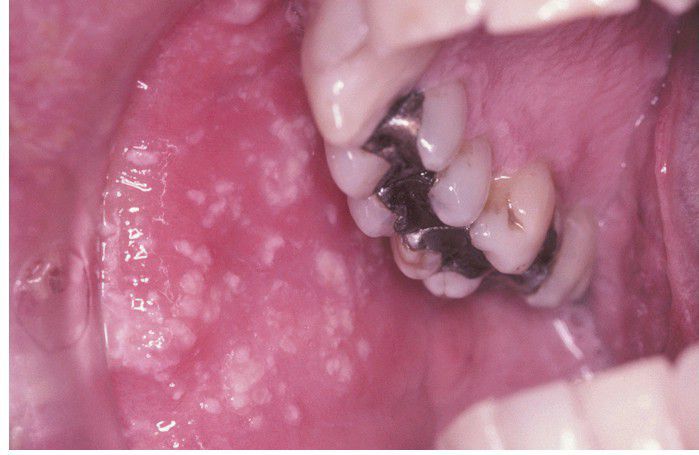

Herpes Zoster

. Numerous white opaque vesicles on the right buccal mucosa.